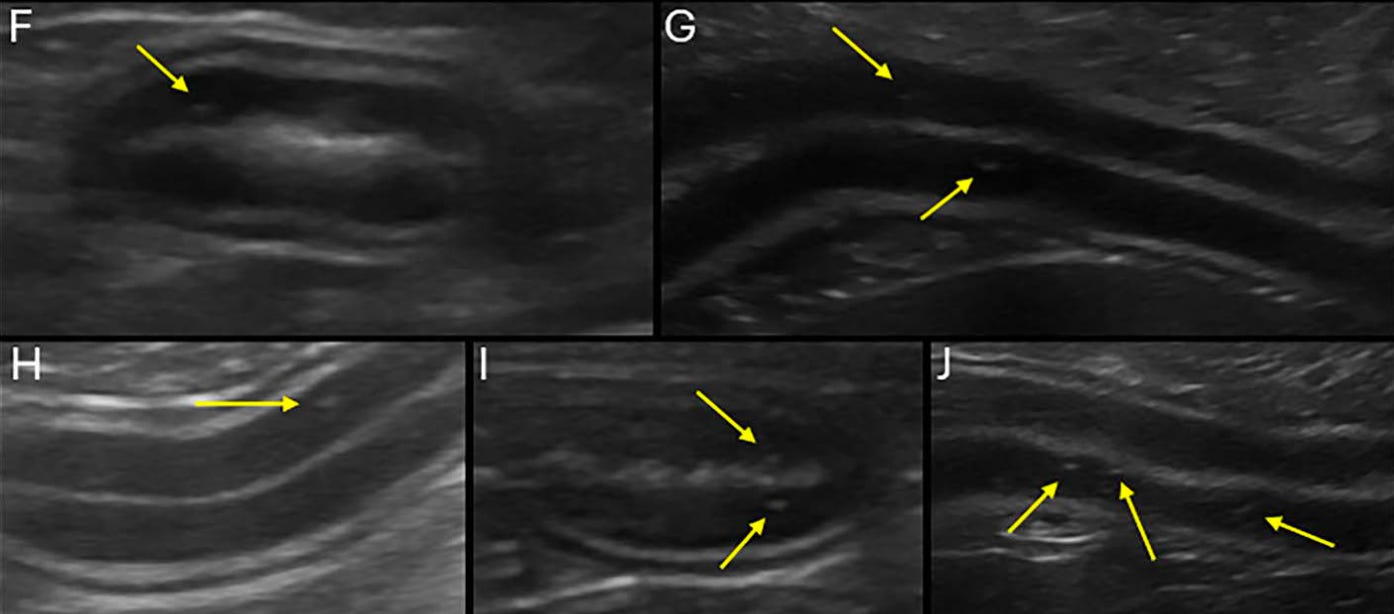

Diferentes grados de punteados hiperecogénicos de la mucosa:

Hasta el 93% de los perros con EPP tienen alteraciones ecográficas en el ID, incluyendo líquido libre peritoneal (73-79%), estrías o punteados mucosos (47-91%), linfadenopatía (18-40%) y dismotilidad o distensión del ID (10-23%).

Estos no se correlacionan con la gravedad de la EPP o los requisitos de tratamiento, pero pueden asociarse con los resultados.

Las estrías hiperecogénicas tienen una sensibilidad del 75% y una especificidad del 96% para la linfangiectasia intestinal que causa EPP, pero los punteados hiperecogénicos son hallazgos no específicos.